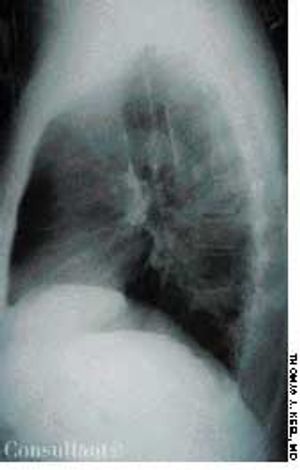

The wife of an 82-year-old man with Alzheimer's disease was concerned about her husband's poor posture. According to the woman, the patient had never sustained a back injury and had always maintained a sedentary lifestyle. He never smoked cigarettes and did not use alcohol. His history included multiple transient ischemic attacks (TIAs).